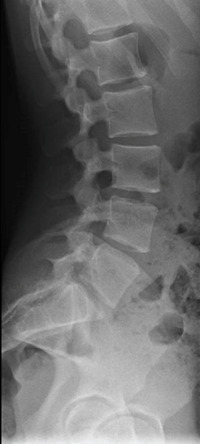

Les radiographies réalisées ne révèlent aucune anomalie (fig. 1). Le scanner demandé secondairement montre une lyse isthmique bilatérale en L3 prédominant à gauche (fig. 2).

L’examen complémentaire de base est la radiographie standard du rachis lombaire de face, de profil et de trois quarts, mais elle ne permet pas toujours de poser le diagnostic. Ainsi, en cas de normalité du bilan radiographique, mais d’un interrogatoire et d’un examen clinique évocateurs, le recours à la tomodensitométrie est nécessaire.